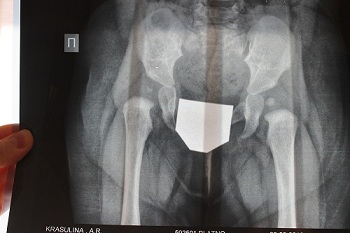

Я так понимаю, Принцессе почти 7 месяцев? :) Я думаю щелчок никак не связан с ношением шины. Чтобы полноценно ответить на ваши вопросы, мне бы хотелось посмотреть на рентгенограмму. Попробуйте сфотографировать ее, и прицепить к письму.

Дмитрий Олегович Сагдеев

и еще вопросик - нет ли на снимке неправильной укладки?

Лесик

Я думаю, щелчок скорее всего был, просто вы не акцентировали на нем внимание. Он происходит при размыкании суставных поверхностей, это признак нестабильности сустава. Посмотрев рентгенограмму, я рекомендовал бы вам вместо перинки Фрейка, шину Виленского. Полностью исключите нагрузку на ноги.